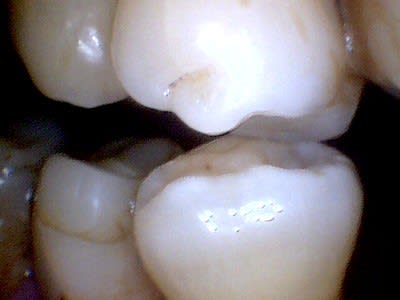

Après hémostase, stérilisation et vitrification, la carbonisation est facilement éliminée aux US et si besoin avec du Negatol (un antiseptique). Cette carbonisation peut être évitée et son importance dépend du matériau ou du tissu traité, elle peut aussi servir à la détection de dentine infiltrée. Les protéines sont déstructurées à 60°, l’effet thermique en mode superpulse ou chopérisé est bactéricide et la puissance crête peut atteindre 200W mais son absorption reste très limitée (0.1mm) donc sans danger pour la pulpe.

De plus, l’état de surface ainsi obtenu offre un meilleur ancrage tout en assurant une bonne herméticité et génère une biostimulation. Voici pour exemple un cas, sans carbonisation, réalisé ce matin pour rééquilibration occlusale par ajout de composite sur composite préexistant (patient ayant subi une ostéotomie sagittale maxillaire Lefort 1).